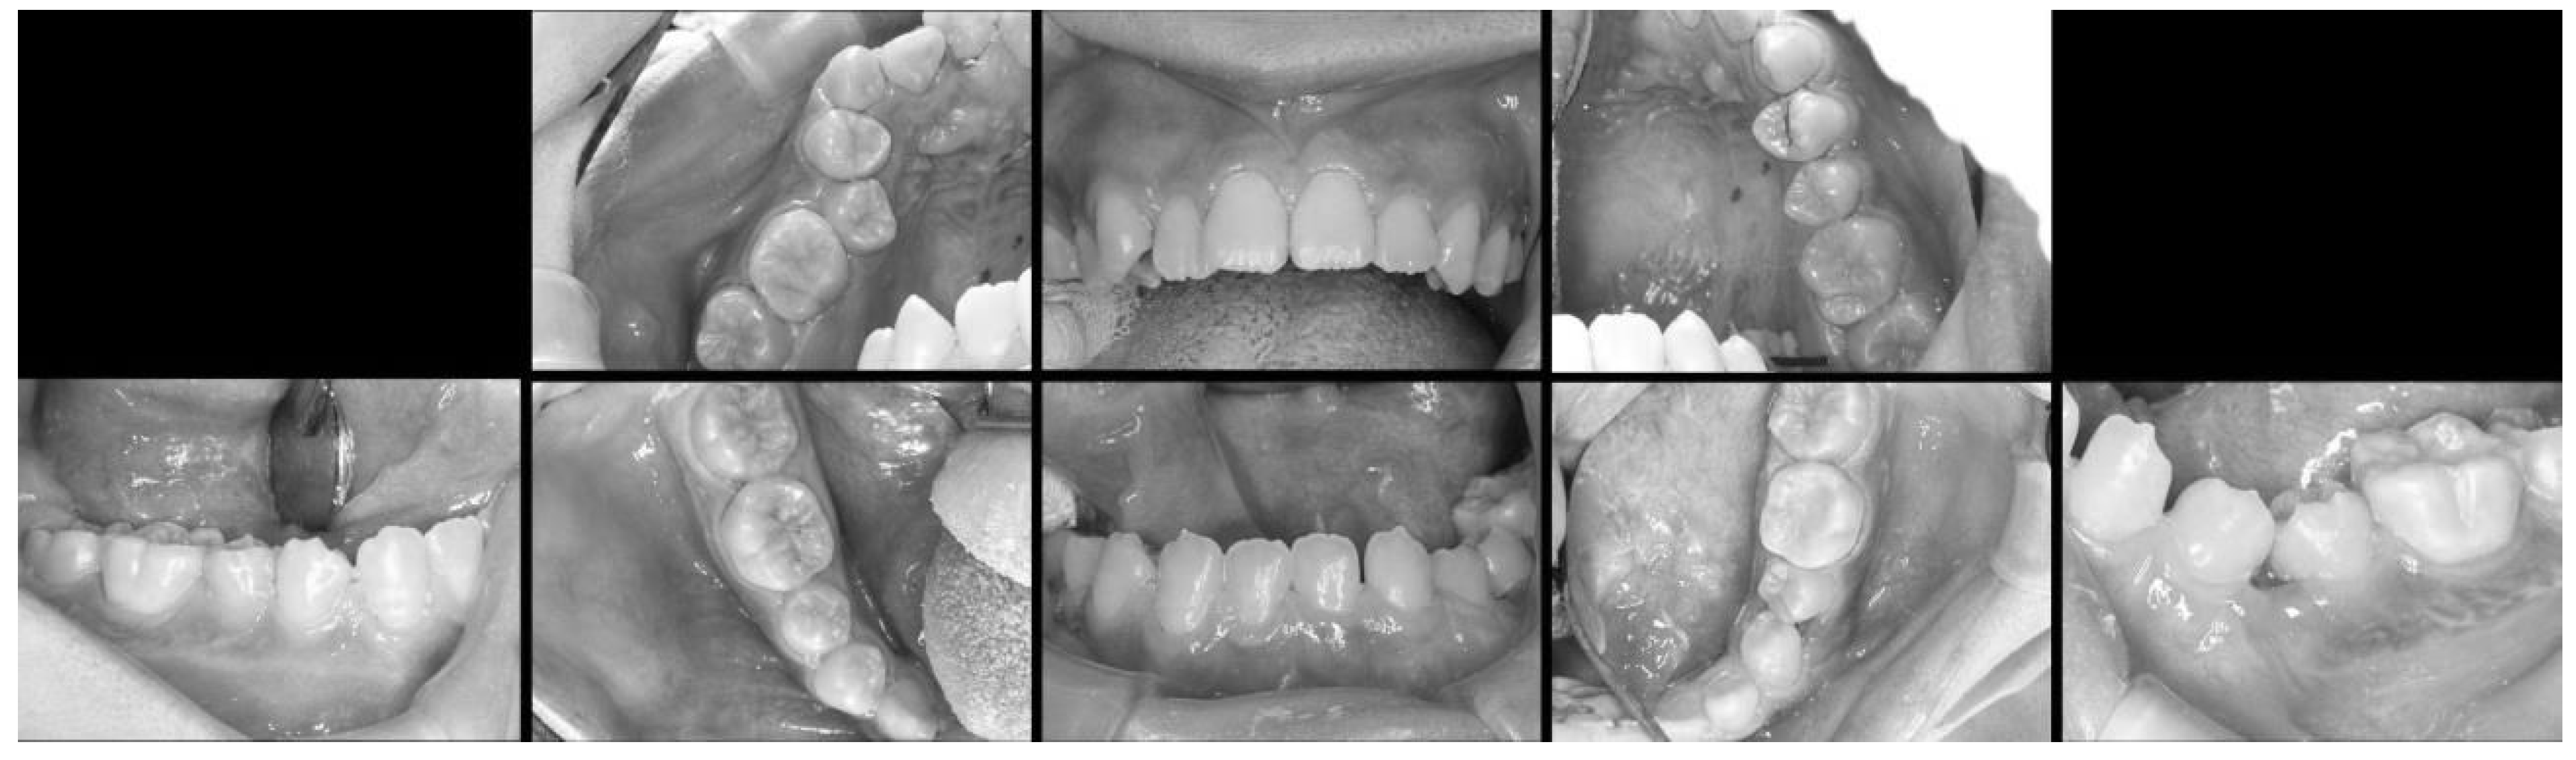

Figure 3.

Intraoral images obtained under general anesthesia. These revealed two missing congenital lateral mandibular incisors.